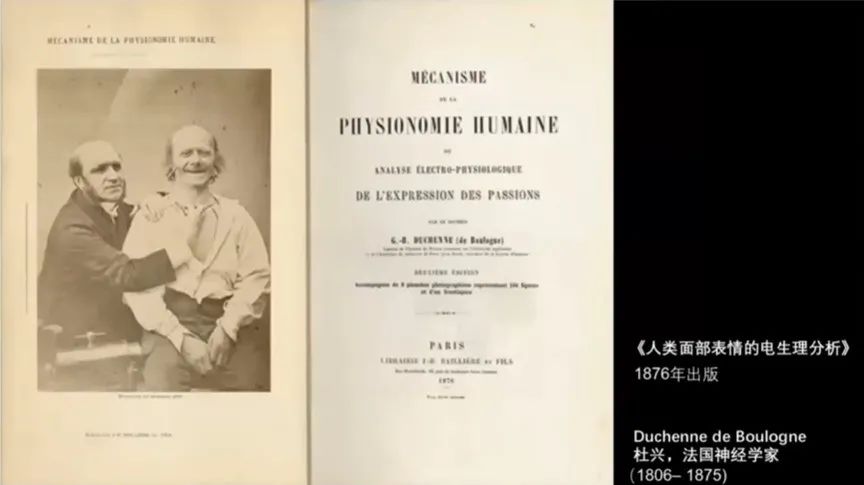

《人类面部表情的电生理分析》,一本在1876年出版的关于人类面部表情的电生理分析的书。这本书在医学史上很著名,杜兴也是法国当时有名的神经学家。我们来看看这本书当中的一段文本。我就不去具体展开它了,我们看它所展示的最终实验结果。在被试的面部表情中,遮罩的一边是自发的表情,另一边是在电击刺激下产生的表情,杜兴对两边不同的表情进行了解释。

在这里,左边的脸是一种悲伤的表情,右边的脸是一种狂喜的表情。杜兴就在因果关系之下去解释一个人受到电击刺激时面部表情的反应。他还特意找来一个雕塑以进行解释,他说,“你看,阿罗蒂诺的额头和眉毛的外观不协调,所谓不协调就是额头和眉毛在因果关系上是相互排斥的。”他特意把这里的不协调之处标注了出来,他认为应该把眉骨的这个地方抹平,这个时候它与额头就符合因果关系了。